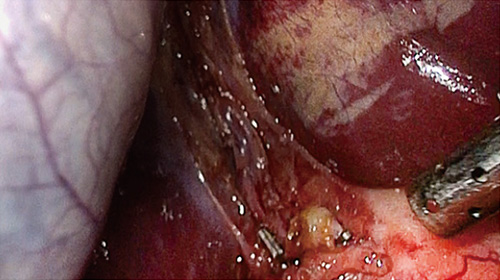

さまざまな医療映像を高精細・高画質で細部までクリアに映し出せる本機は、高い精度が求められる手術や検査時の視認性向上に貢献します。

本シリーズは、4K(3840×2160ピクセル)の高解像度LCDパネルとMini LEDバックライトを搭載しています。細かいエリアでの明暗調整が可能になり視認性が向上することに加え、バックライトに独自のローカルディミング(部分駆動)技術「Backlight Master Drive」を用いて、高いピーク輝度(LMD-27M1MD:2,250cd/m2、LMD-32M1MD:1,850cd/m2、LMD-43M1MD:2,000cd/m2)と100万:1の高コントラスト比を実現しています。

HLG(Hybrid Log-Gamma)及びPQ (Perceptual Quantization)準拠の信号を入力し、色調調整メニューでガンマをHLGもしくはPQに設定することで、HDR信号の明部と暗部の再現性を細部まで向上させた表現が可能になります。また、4Kの放送規格であるITU-R BT.2020に準拠した広色域に対応しています。

モニター前面に内蔵した明るさセンサーが手術室内の照明環境を検知して、モニターの明るさを自動的に調整します。手術中にICG*を使用するなど、暗い照明へ変化するケースでも視認性を確保することができます。